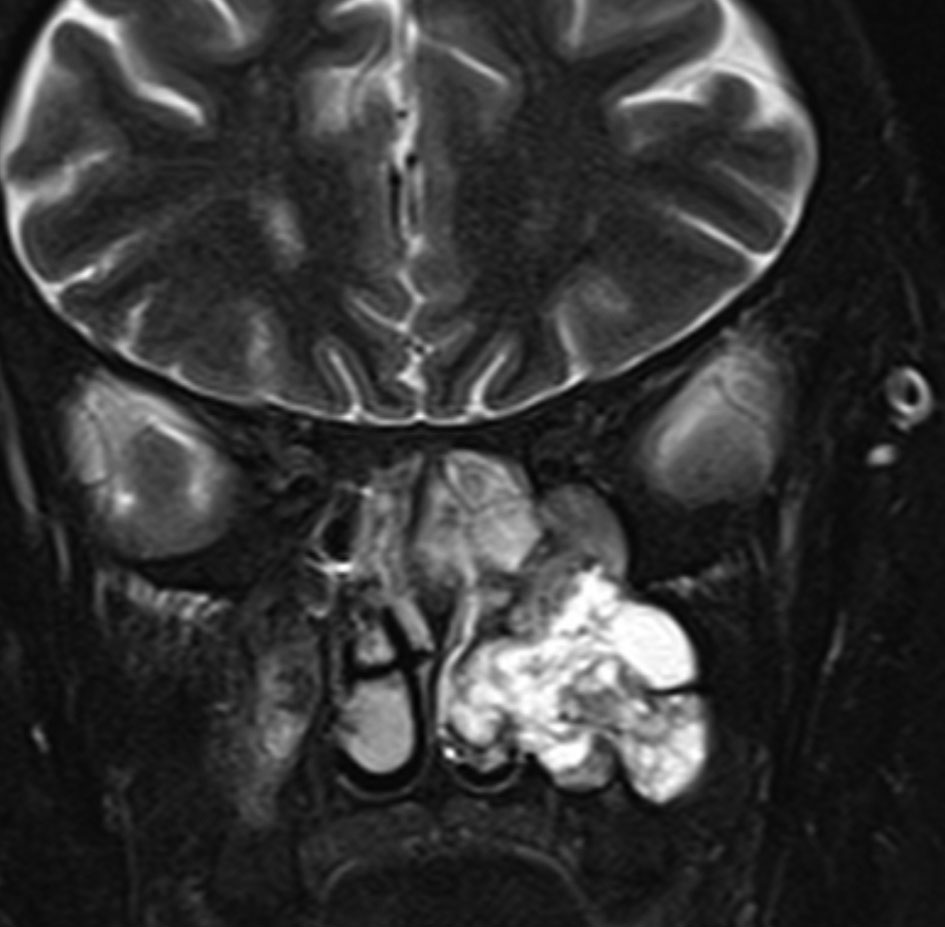

メッケル腔(ガッセル神経節)という場所から発生した三叉神経鞘腫のMRIです。サイズは放射線治療するには大きすぎます。ですから手術摘出します。手術には側頭開頭硬膜外法と経鼻内視鏡手術があります。内視鏡手術は三叉神経が外側に来ているので優位性があります。開頭手術では,側頭部の前の方を小さく開頭して脳の硬膜の外から腫瘍を見るだけで取れます。もちろん脳の損傷は起こさないようにしなければなりません。手術中には三叉神経が薄く広がって腫瘍のまわりにくっついていますからそれを大事に守りながら腫瘍を取っていきます。

手術のすぐ後のMRIです。幸いなことにこの患者さんでは,腫瘍を全部取ったのですが三叉神経の大部分を残すことができて,顔のしびれはとても軽くてすみました。全摘出すると経鼻手術でも開頭手術でも多少の顔面の痺れ(感覚低下)はでますが,日常生活に支障のないレベルに留めなければなりません。